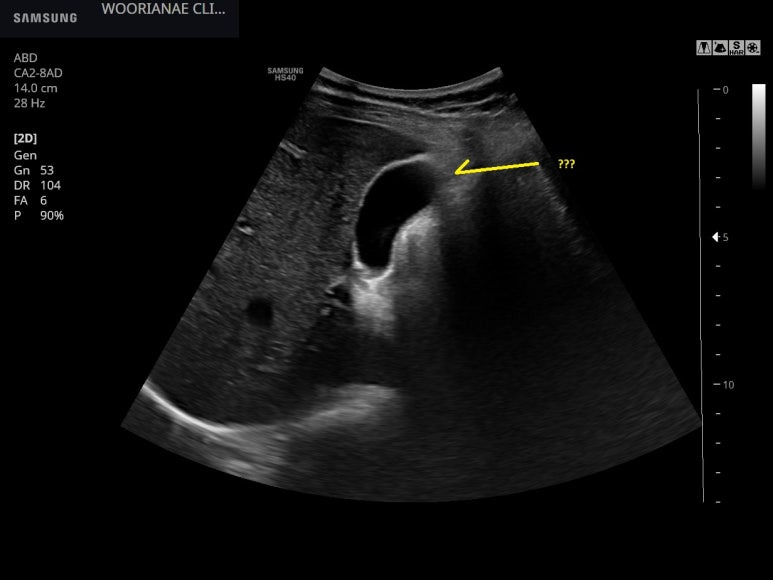

과거에 담낭염인데 수술은 하지 않았었다?

작년말 잠시 귀국하여 회사검진에서 담낭벽이 두껍다고 결과를 받았다. "그곳은 검진만 하는 곳인데.." *&^%$

이런 모습이라도 있는건지?

담석증, 담낭 산통 감별위해 초음파, 담낭 선근종증 (segmental type), 짧은 추적 계획 - 동대문구 답